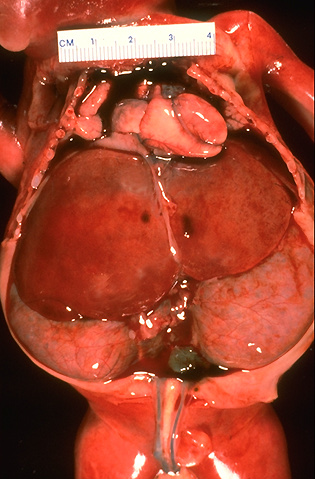

| This infant died soon after premature birth at 23 weeks gestation from pulmonary hypoplasia as a result of oligohydramnios. The oligohydramnios resulted from markedly diminished fetal urine output as a consequence of polycystic kidney disease. Note the bilaterally enlarged kidneys that nearly fill the abdomen below the liver. The histologic appearance in this case, coupled with the gross appearance., was consistent with autosomal recessive polycystic kidney disease (ARPKD). |